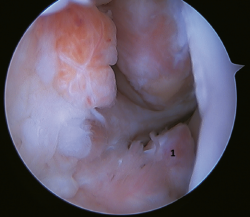

The main indication for this repair is rupture of the upper fascicle of the ATFL from its fibular insertion, with good tissue quality of the remaining ligament (Figure 3).

Figure 3. A: identification of the fibular insertion of the ATFL (*) with excellent quality of the tissue remnant; B: technique with two knotless implants and using a modified single anterolateral portal; C: final result. P: fibula; T1: talofibular tunnel; T2: calcaneofibular tunnel.